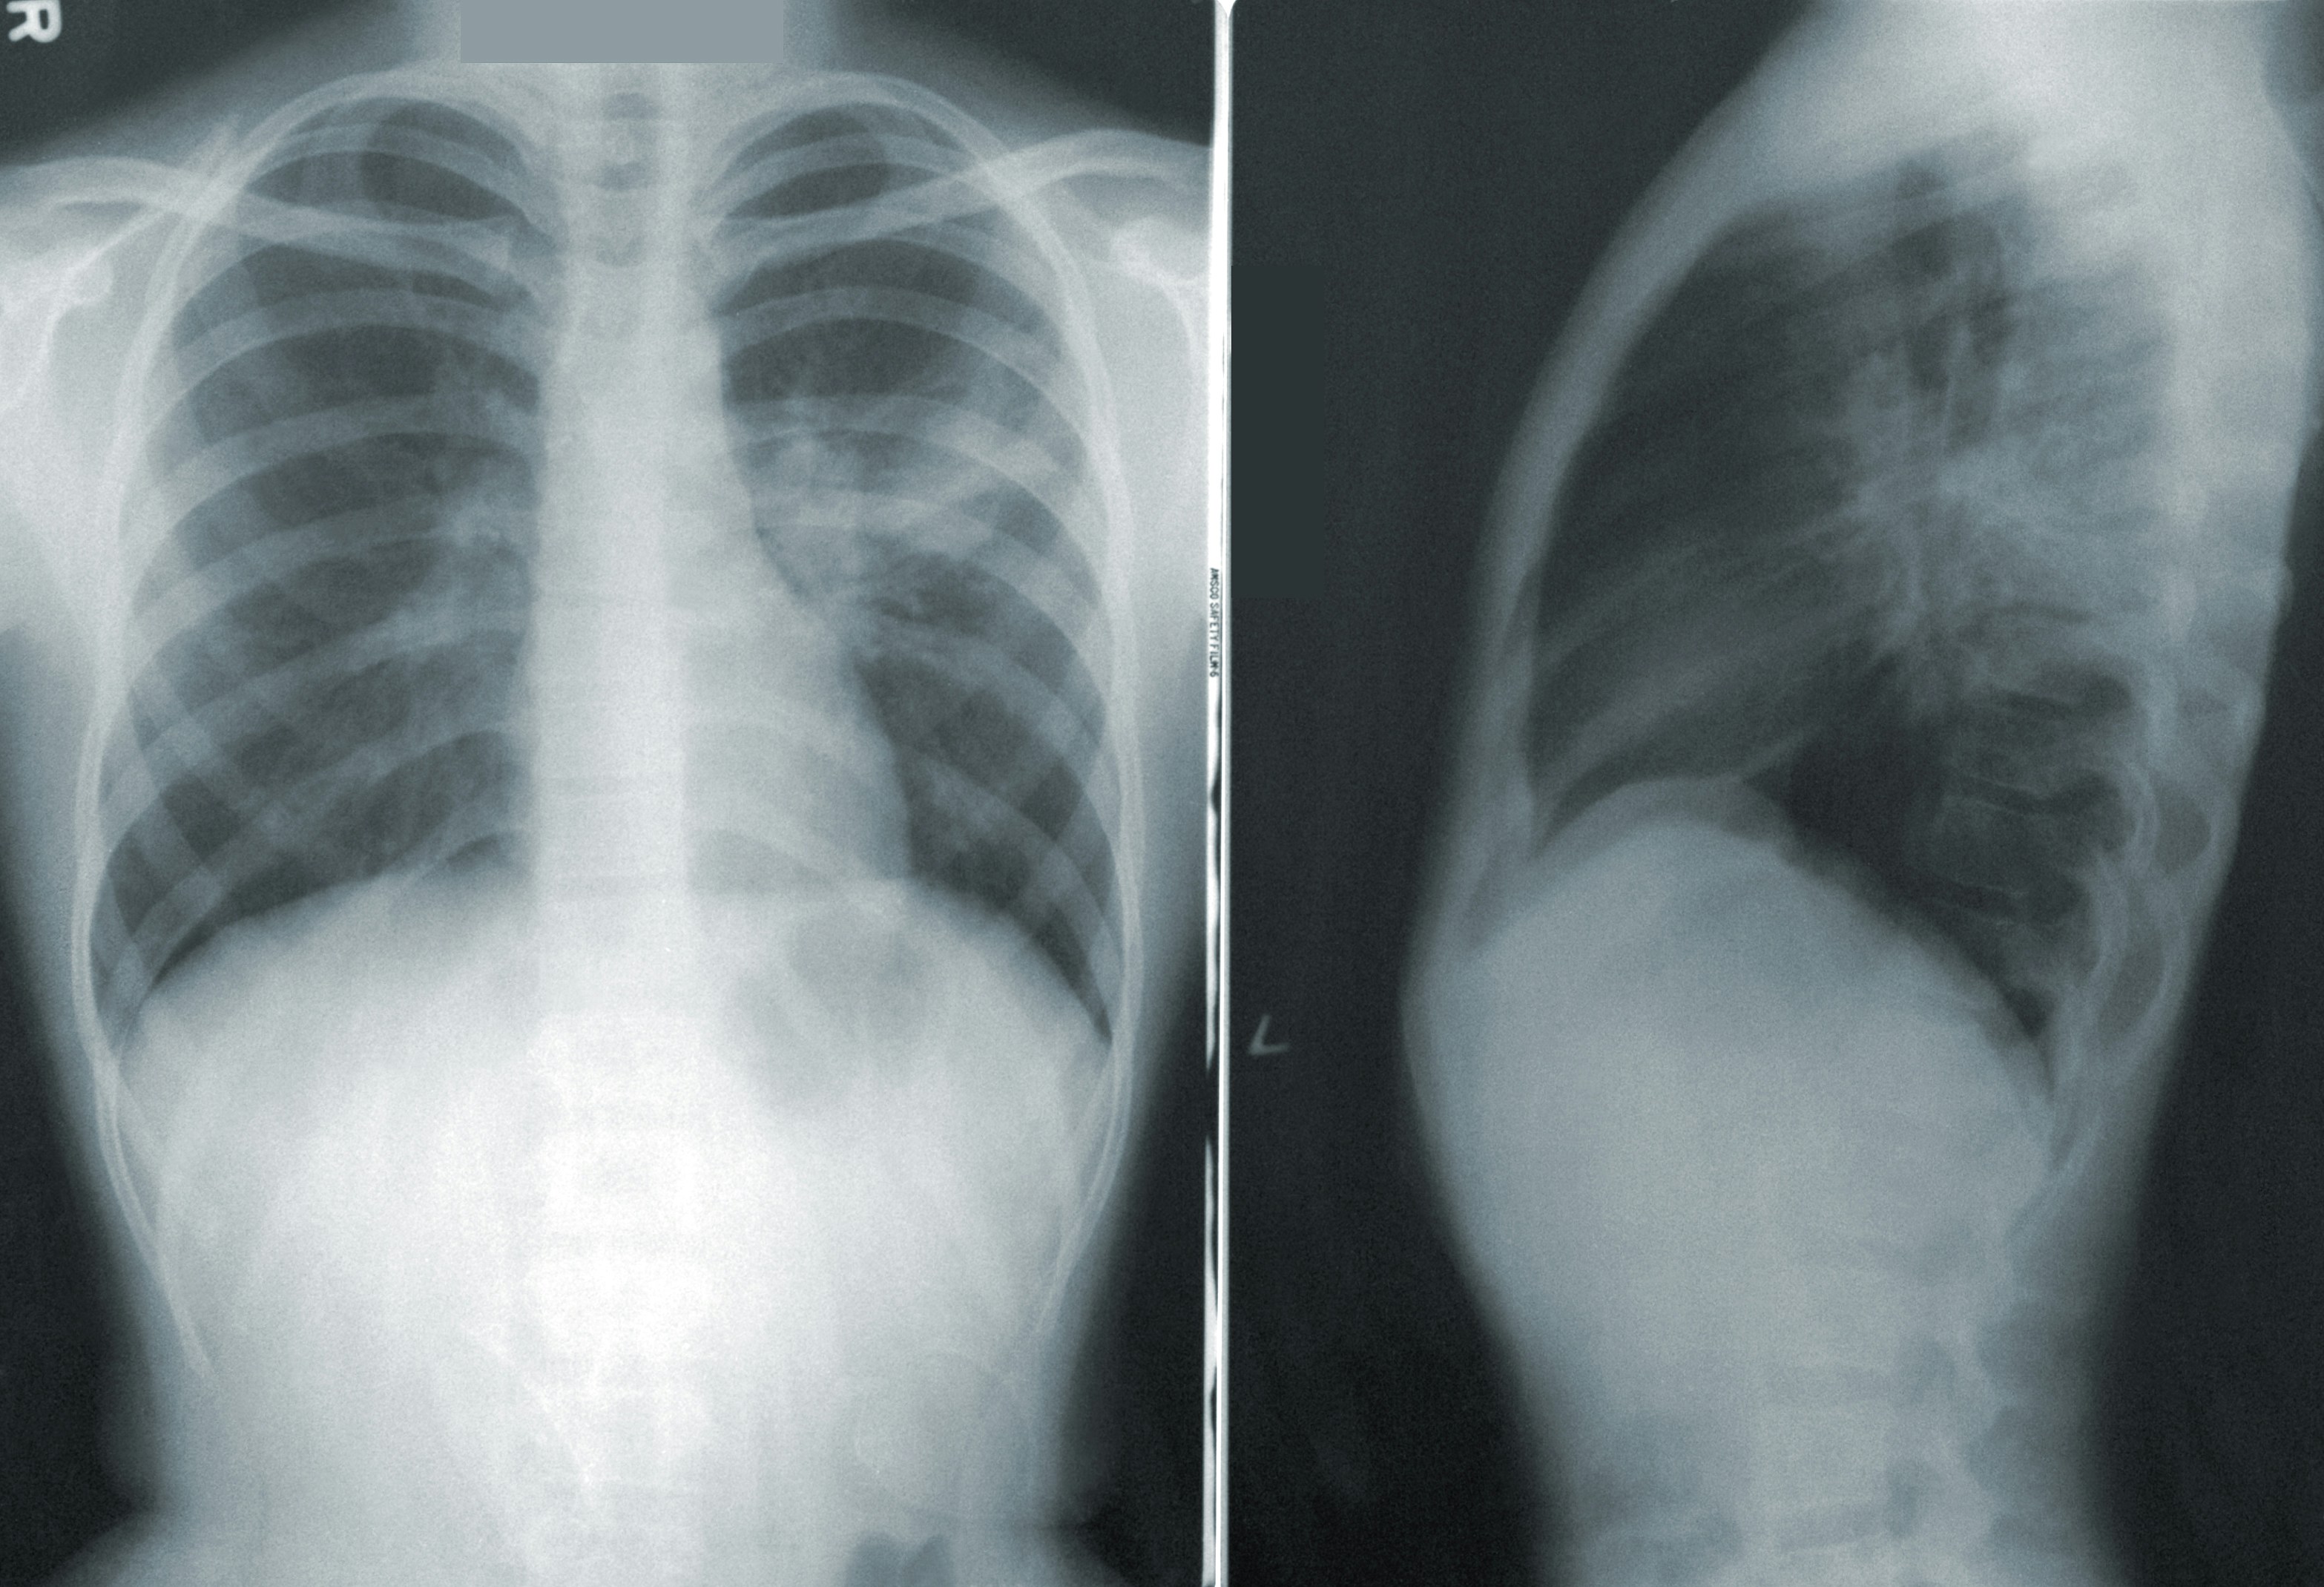

Photo by CDC on Unsplash